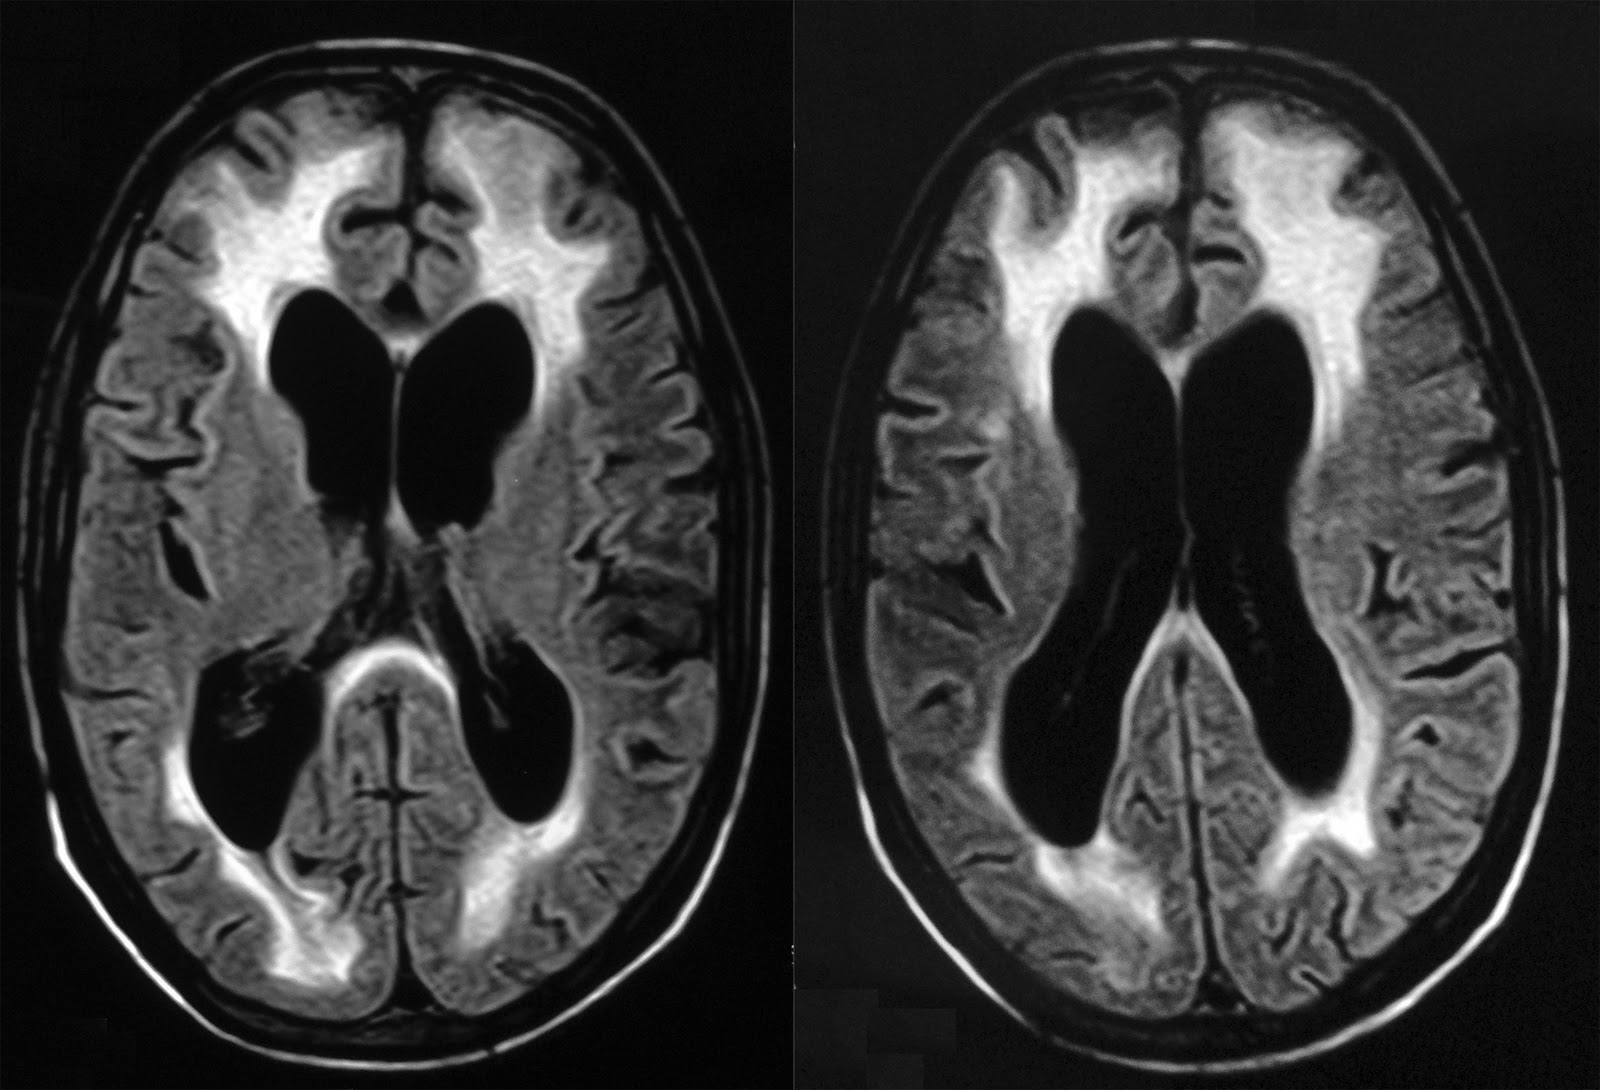

From www.sciencephoto.com

Brain atrophy in HIV/AIDS, MRI scans Stock Image C058/2245 Brain Damage From Aids Inflammation in the brain causes cognitive problems,. Hiv encephalopathy is a serious complication of hiv that usually develops when hiv progresses to aids. Hiv also triggers inflammation that may damage the brain and spinal cord (central nervous system) and cause symptoms such as: As hiv invades the brain, a powerful inflammatory response is activated that can cause neurological deficits. Hiv. Brain Damage From Aids.

HIVinduced cerebral injury. Notes (A) Volume loss. HIVinfected Brain Damage From Aids While hiv primarily affects the immune system, it can lead to a wide range of severe neurological disorders, particularly if hiv. Sometimes hiv can damage certain sections of the brain, which can lead to mild cognitive (thinking) problems. Hiv encephalopathy is a serious complication of hiv that usually develops when hiv progresses to aids. As hiv invades the brain, a. Brain Damage From Aids.